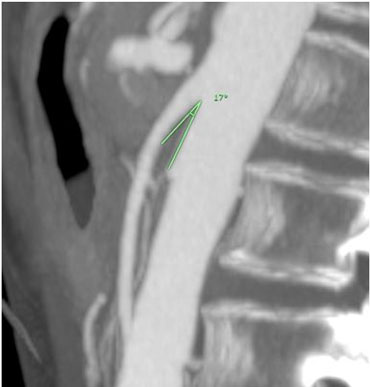

A free-fall nasogastric tube was installed to improve symptoms. A colonoscopy describes mild nonspecific distal ileitis, biopsies reported moderate active chronic ileitis, with subtotal villous atrophy. Computed tomography angiography showed no evidence of intestinal obstruction or mesenteric ischemia. Given the suspicion of SMAS, the images are reviewed in a targeted manner with a radiologist, identifying a decrease in the aorto-mesenteric angle of 14° (Figure 5) and a decreased aorto-mesenteric distance of 6.9 mm (Figure 6). During her hospitalization, the patient received mixed nutrition, oral and parenteral. A liquid, fractionated diet was started and postural changes were suggested during oral feeding to promote the passage of intestinal contents through the duodenum. Oral tolerance improved, but isolated episodes of vomiting persisted. Installation of a nasojejunal tube was suggested to maintain nutritional support at home, but the patient rejected this measure due to the progression of her underlying disease and the desire to remain without invasive measures at home. She was discharged after four weeks of hospitalization, with a 2 kg weight gain and better oral tolerance.

Figure 5: Reduced aorto-mesenteric angle in patient no. 2, sagittal view.